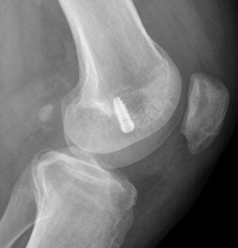

Fig 132. Mala orientación del túnel femoral.

A: Rx lateral. Túnel muy vertical y ocupando la parte media del cóndilo.